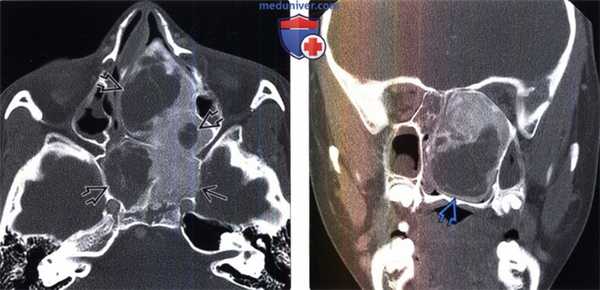

(Слева) При КТ в костном окне в корональной проекции определяется утолщенная чешуя височной кости неоднородной плотности. Также наблюдается утолщение клиновидной кости неоднородной плотности. В теле нижней челюсти определяется преимущественно кистозный (фиброзный) очаг поражения.

(Справа) При аксиальной КТ в костном окне у этого же пациента с полиоссальной фиброзной дисплазией определяются смешанные рентген прозрачные и склеротические изменения кости. Обратите внимание: шов резко разграничивает зоны различных изменений кости, что характерно для фиброзной дисплазии.

(Слева) При КТ в костном окне в аксиальной проекции определяется смешанная склеротическая и рентгенпрозрачная фиброзная дисплазия клиновидной кости и верхней челюсти. Обратите внимание на сужение левой крыловидно-верхнечелюстной щели. Дефект коркового слоя верхней челюсти - след выполненной ранее биопсии.

(Справа) При корональной КТ в костном окне у пациента с фиброзной дисплазией определяется обширное поражение тела клиновидной кости и крыловидных отростков. Отмечается также выраженное сужение левого видиевого канала, смещение и небольшое сужение левого круглого отверстия.